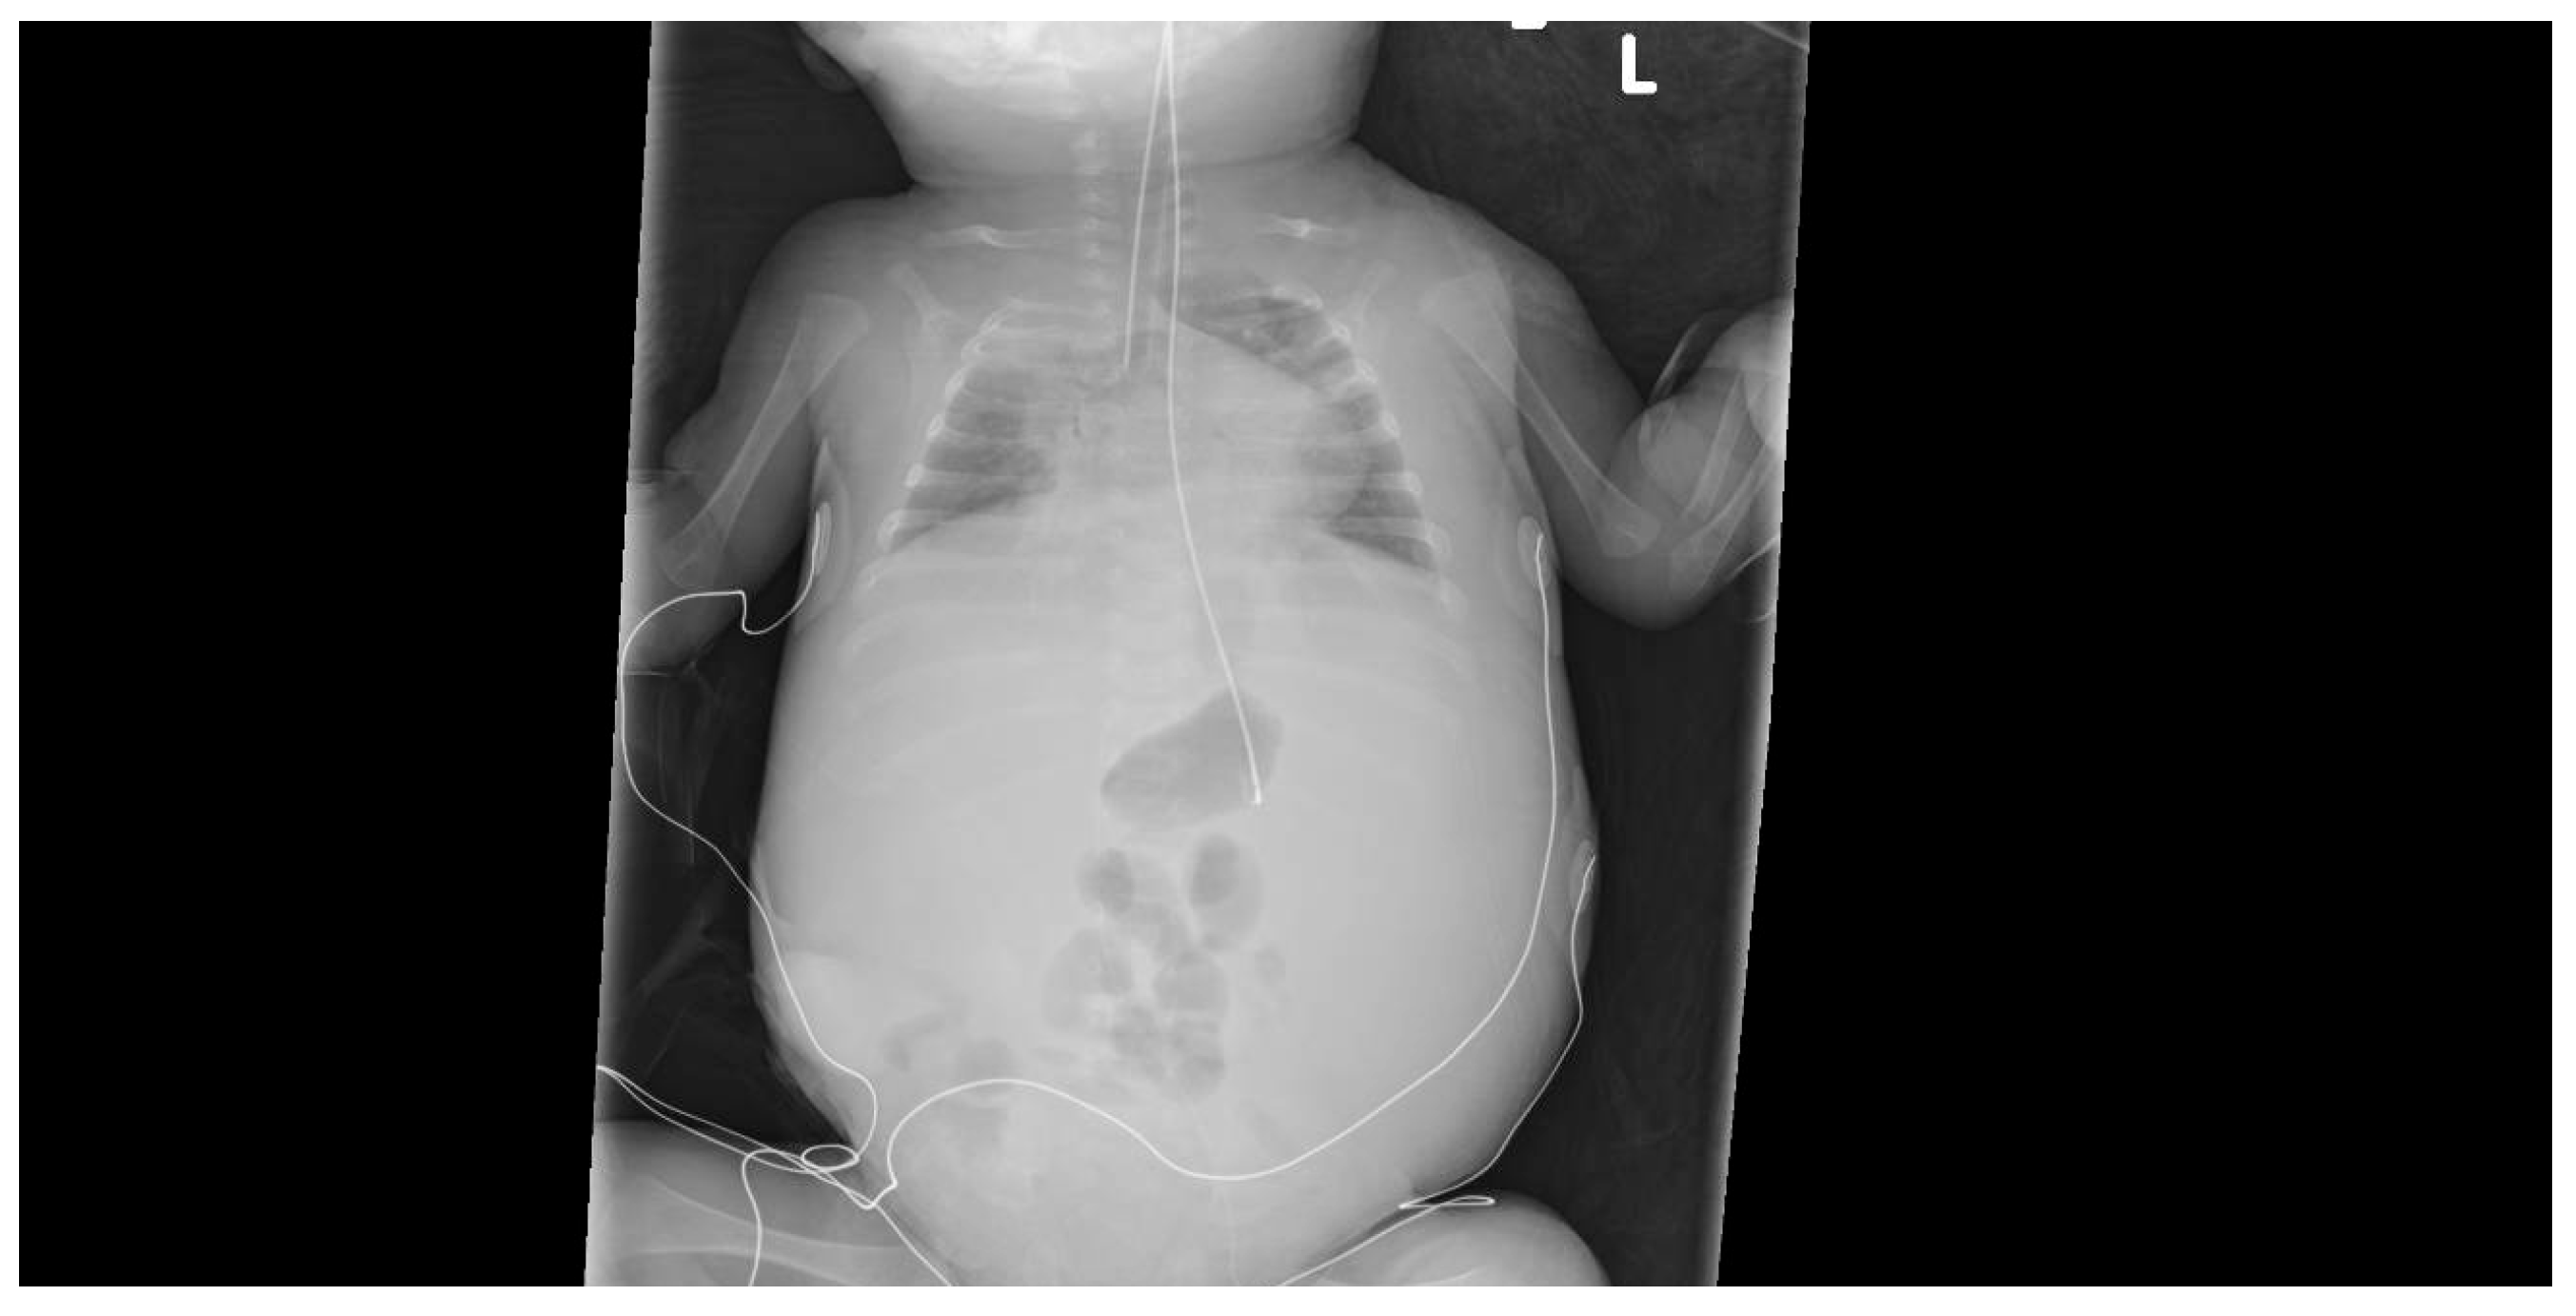

2. Case Presentation